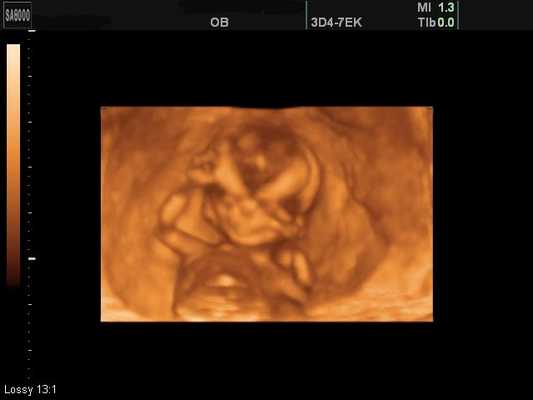

1. Наиболее сильное воздействие на плод оказывают доплерография, трехмерное 3Д и 4Д ультразвуковое исследование во все сроки беременности с записью ультразвука на цифровом носителе и распечаткой изображения ребенка на термопринтере и вагинальное ультразвуковое исследование.

3D/4D ультразвуковое исследование (УЗИ) на современном этапе хорошо известно. Не вызывает сомнения тот факт, что этот метод открывает новые возможности исследования в акушерстве и гинекологии, особенно при обследовании плода [1, 2]. Однако все еще возникают споры о целесообразности применения объемного ультразвука. Обычно выдвигается тезис о том, что 2D эхография является достаточной для достижения цели в диагностике, а трехмерная лишь "декорирует" обнаруженное патологическое состояние или просто красиво демонстрирует изображение органов или объектов. Нельзя не согласиться с тем, что двухмерный ультразвук является базисом современной эхографии и, благодаря ему, врачи достигли больших успехов в решении множества клинических задач в акушерстве, диагностике заболеваний и пороков развития у плода [1, 3]. Вместе с тем было бы наивно полагать, что все проблемы диагностики решены и не следует развивать новые методики на практике, внедряя их в решение рутинных задач или для повышения точности обнаружения и детализации аномалий.

Основные принципы работы приборов и датчиков для проведения 3D/4D УЗИ изложены во множестве монографий и руководств [1, 4]. Однако хотелось бы остановиться на ряде важных усовершенствований, появившихся в объемном ультразвуке в последние годы. Уже несколько десятилетий известна возможность получения трехмерных изображений при помощи УЗИ. Для клинического применения объемный метод стал привлекательным после появления трехмерного ультразвука, работающего в режиме реального времени - 4D. Этот режим позволил не только быстро получить изображение для последующей визуальной оценки, но и повысить его реальное качество благодаря возможности оперативной коррекции угла сканирования с целью уменьшения артефактов и повышения достоверности изображения. Основные режимы работы большинства современных трехмерных приборов можно представить в виде пяти основных функций: поверхностный режим, мультиплановый, мультиплоскостной, объемный негативный и мультиплоскостной в режиме реального времени (STIC).

Поверхностный режим 3D/4D УЗИ позволил визуализировать поверхности тела плода (лоб, лицо, переднюю поверхность груди, область половых органов, затылок и заднюю поверхность спины, дистальные отделы конечностей, суставы конечностей) при сроках гестации 11-22 недель в большинстве случаев (93%) (рис. 1-4). Затруднения в визуализации отдельных поверхностей были отмечены в 24% из-за особенностей положения плода, расположения конечностей и других частей тела, локализации пуповины, количества околоплодных вод. Двигательная активность плода и многоводие значительно облегчали задачу визуализации поверхностей. Следует также учитывать, что полное отсутствие околоплодных вод во всех случаях не позволило получить информацию о поверхностях у плода в этом режиме. Сложности в получении поверхностных изображений отмечены в 38% случаев при обследованиях плодов после 35 недель гестации.

Рис. 1. Беременность 12 недель (поверхностный режим). Лицо здорового плода.